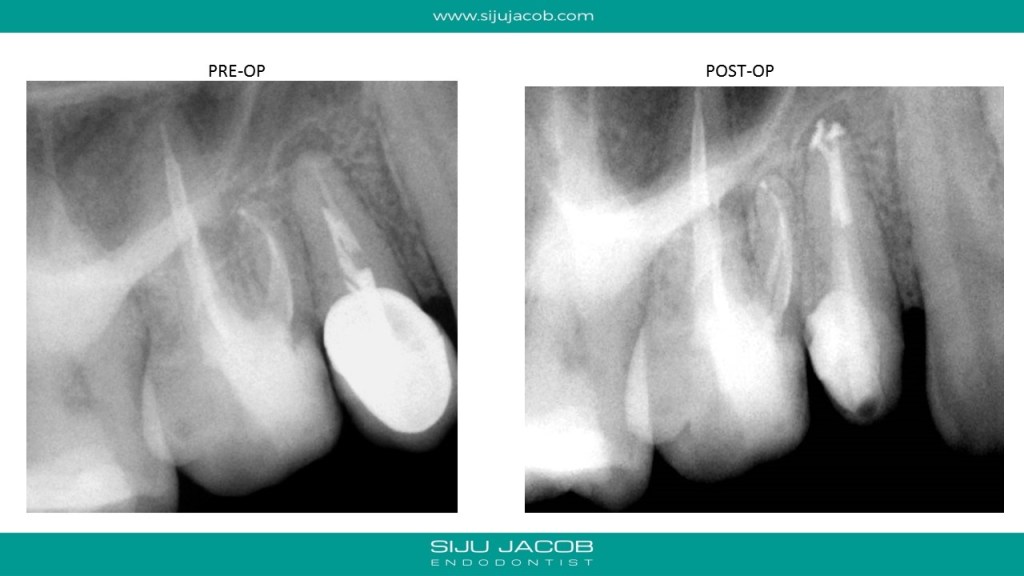

Written by Siju JacobApril 13, 2020 Pre-molar Re-treat with funky anatomy This was a routine Maxillary pre-molar Re-treat. Always nice to see some anatomy being filled in the end. Share this: Share on X (Opens in new window) X Share on Facebook (Opens in new window) Facebook Like Loading... Related Leave a comment Cancel reply Δ